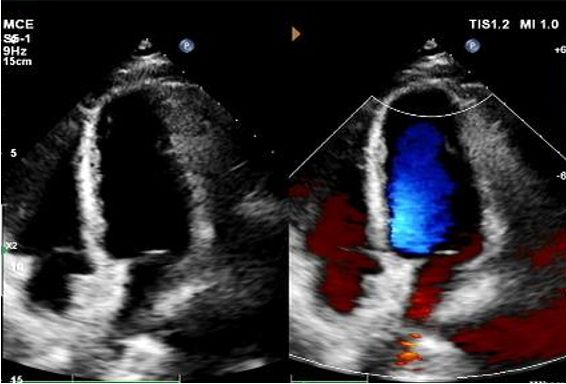

Eco de 1 ano:

No visible disc structures – replaced by 8mm tissue thickening at the septal implant site.

Zero residual shunt (rest or post-Valsalva).

Absorção completa do dispositivo confirmada.